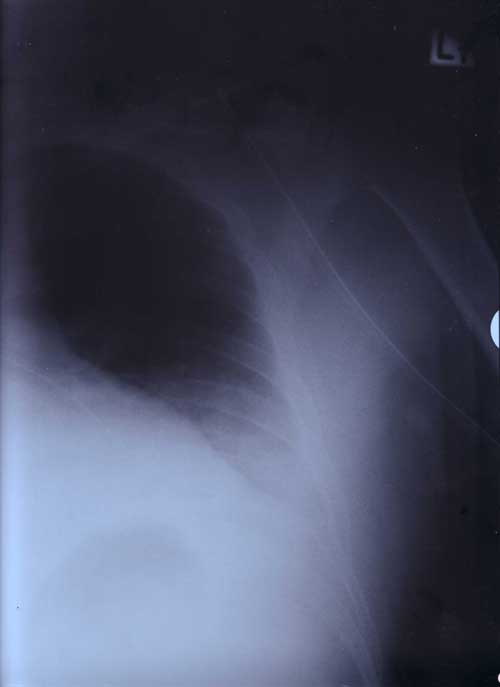

X Rays

21st January 2000